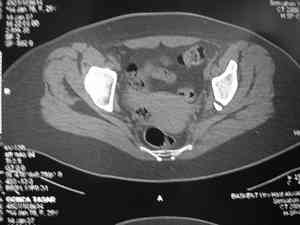

прилагаю пример с такой же давностью травмы, репонировали аппаратом

> в аппарате или одномоментно открыто. Лично я склоняюсь к аппаратному лечению на первом этапе.

задача непростая, если мало опыта в этом деле, подумайте еще раз